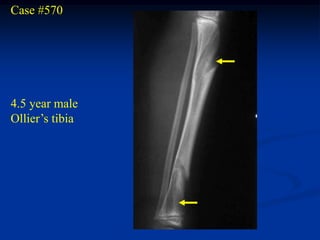

Case #570

4.5 year male

Ollier’s tibia